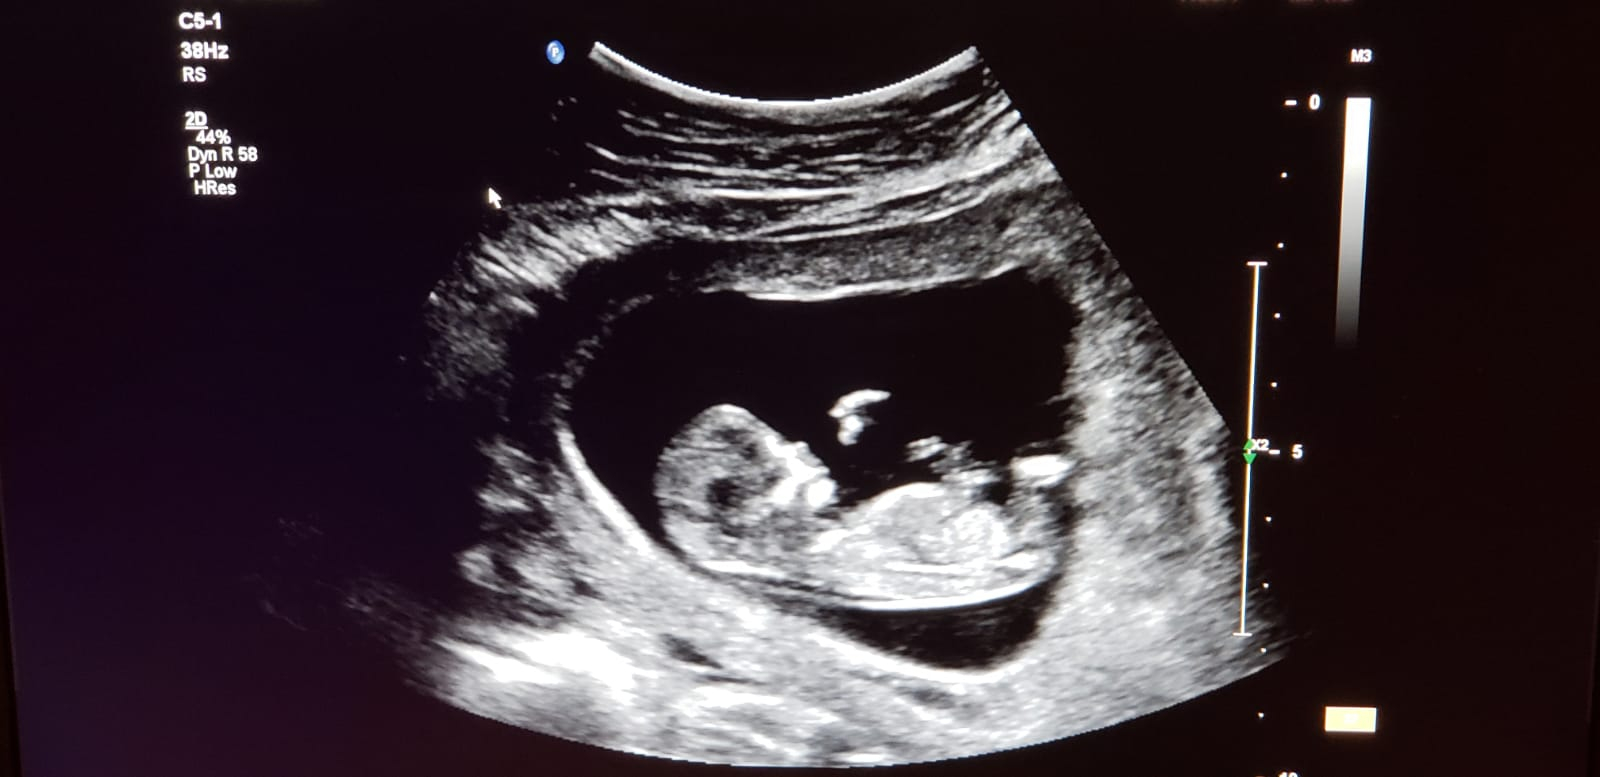

20w6d!! It's 2D, so you can't see much but we're so excited! 151bpm, and doing flips and rolls during the ultrasound!! Doing the gender reveal tomorrow!